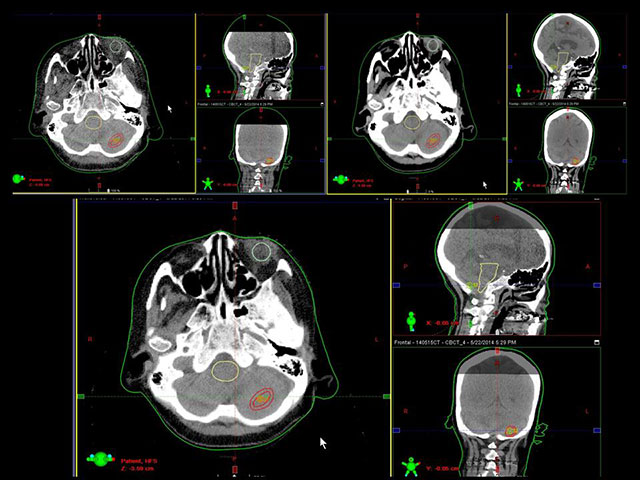

SRT[定位放射線治療]

小さな病変に3次元的に大量の放射線を集中照射し短期間で治療します。周囲の正常組織への被ばくを極力抑え、病変の部分にのみ高線量の照射が可能です。

IGRT[画像誘導放射線治療]

IGRT(画像誘導放射線治療)とは、治療寝台上でX線管球を用いてX線撮影とCT撮影を行い病変部へ正確に治療を行う治療技術です。